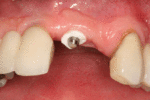

The area of the mouth that is missing a tooth is identified.

An area with a single missing tooth